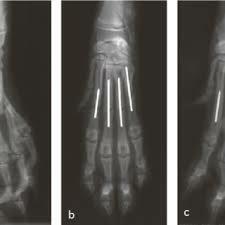

Dowel pinning for metacarpal and metatarsal fractures in dogs

掌骨固定應該是不影響關節

另外記得上課時說RADIUS骨折不可使用IM PIN是因兩端皆為關節 ,然後IM PIN須至少有一段露在致密骨

外面以提供摩擦力所以不能用